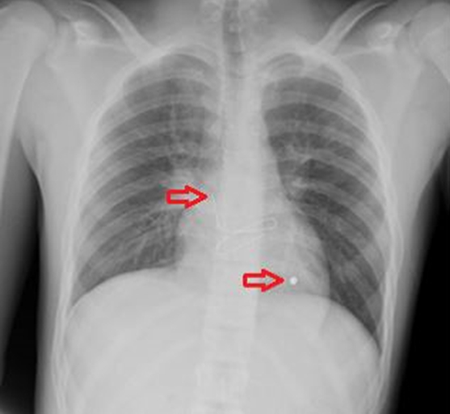

A chest radiograph (Figure 1) was obtained which showed a foreign body overlying the left hemithorax at the level of the apex of the cardiac silhouette.

Figure 1. Arrows pointing to entrance wound marked with a clip and foreign body inside the cardiac silhouette.